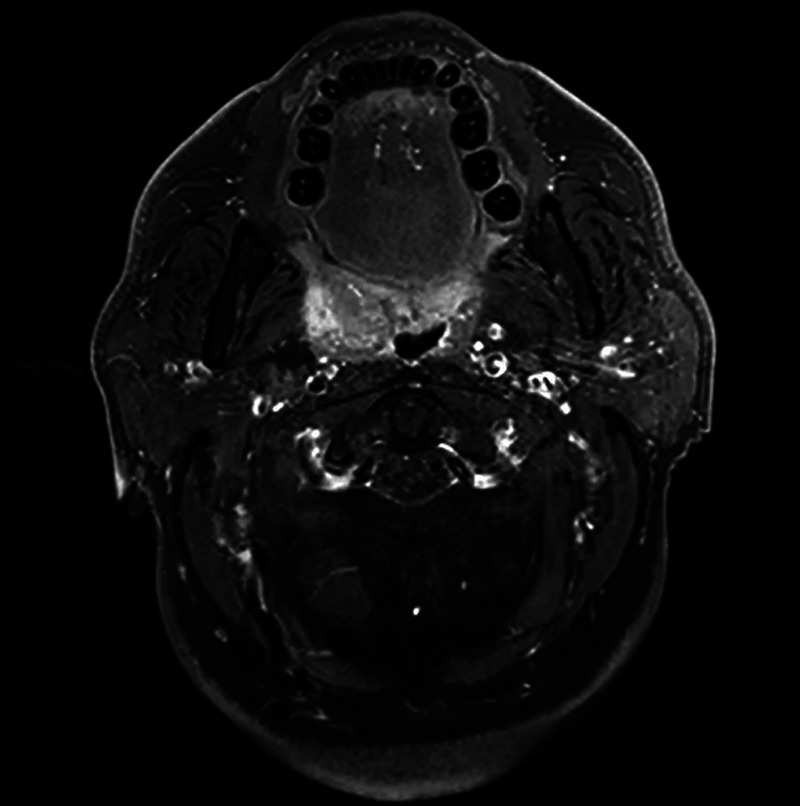

EUS-FNA to diagnose a submucosal oropharyngeal carcinoma.